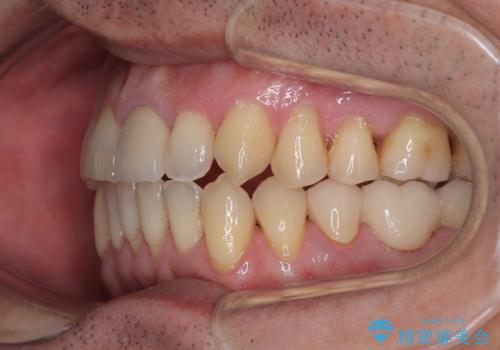

外科処置は希望されなかったので、開咬の改善は限界があると事前にお話ししていたため、上下前歯が完全に接触する前に、もう十分改善したとのことで治療を終了しました。

インビザラインを毎日22時間しっかりと装着してくださったので、我々も驚愕するほどの治療成果が達成されました。